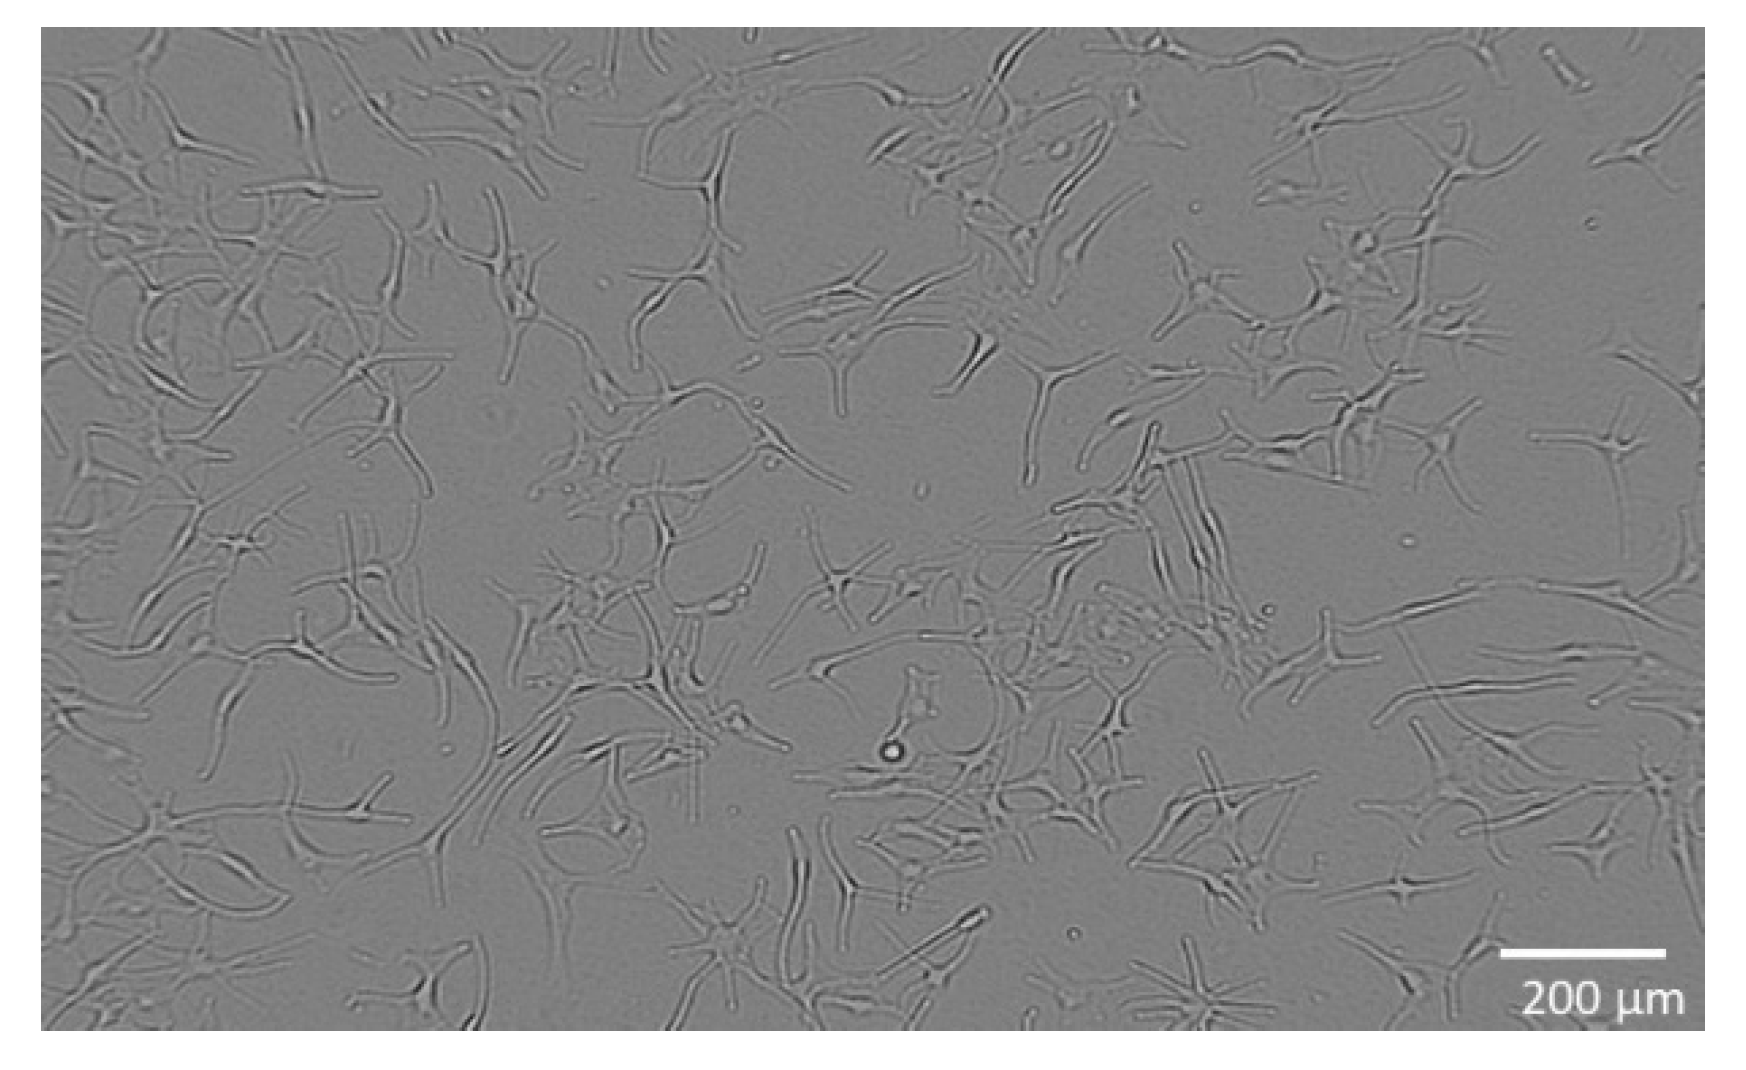

2.3. Metabolic Activity of WM-266-4 Cells and Appoptosis

4.5. Metabolic Activity of WM-266-4 and Normal Human Epidermal Melanocytes

4.6. Determination of Cell Apoptosis